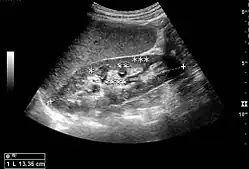

Figure 5. Simple renal cyst with posterior enhancement in an adult kidney. Measurement of kidney length on the US image is illustrated by '+' and a dashed line.[1] -

Figure 6. Complex cyst with thickened walls and membranes in the lower pole of an adult kidney. Measurements of kidney length and the complex cyst on the US image are illustrated by '+' and dashed lines.[1] -